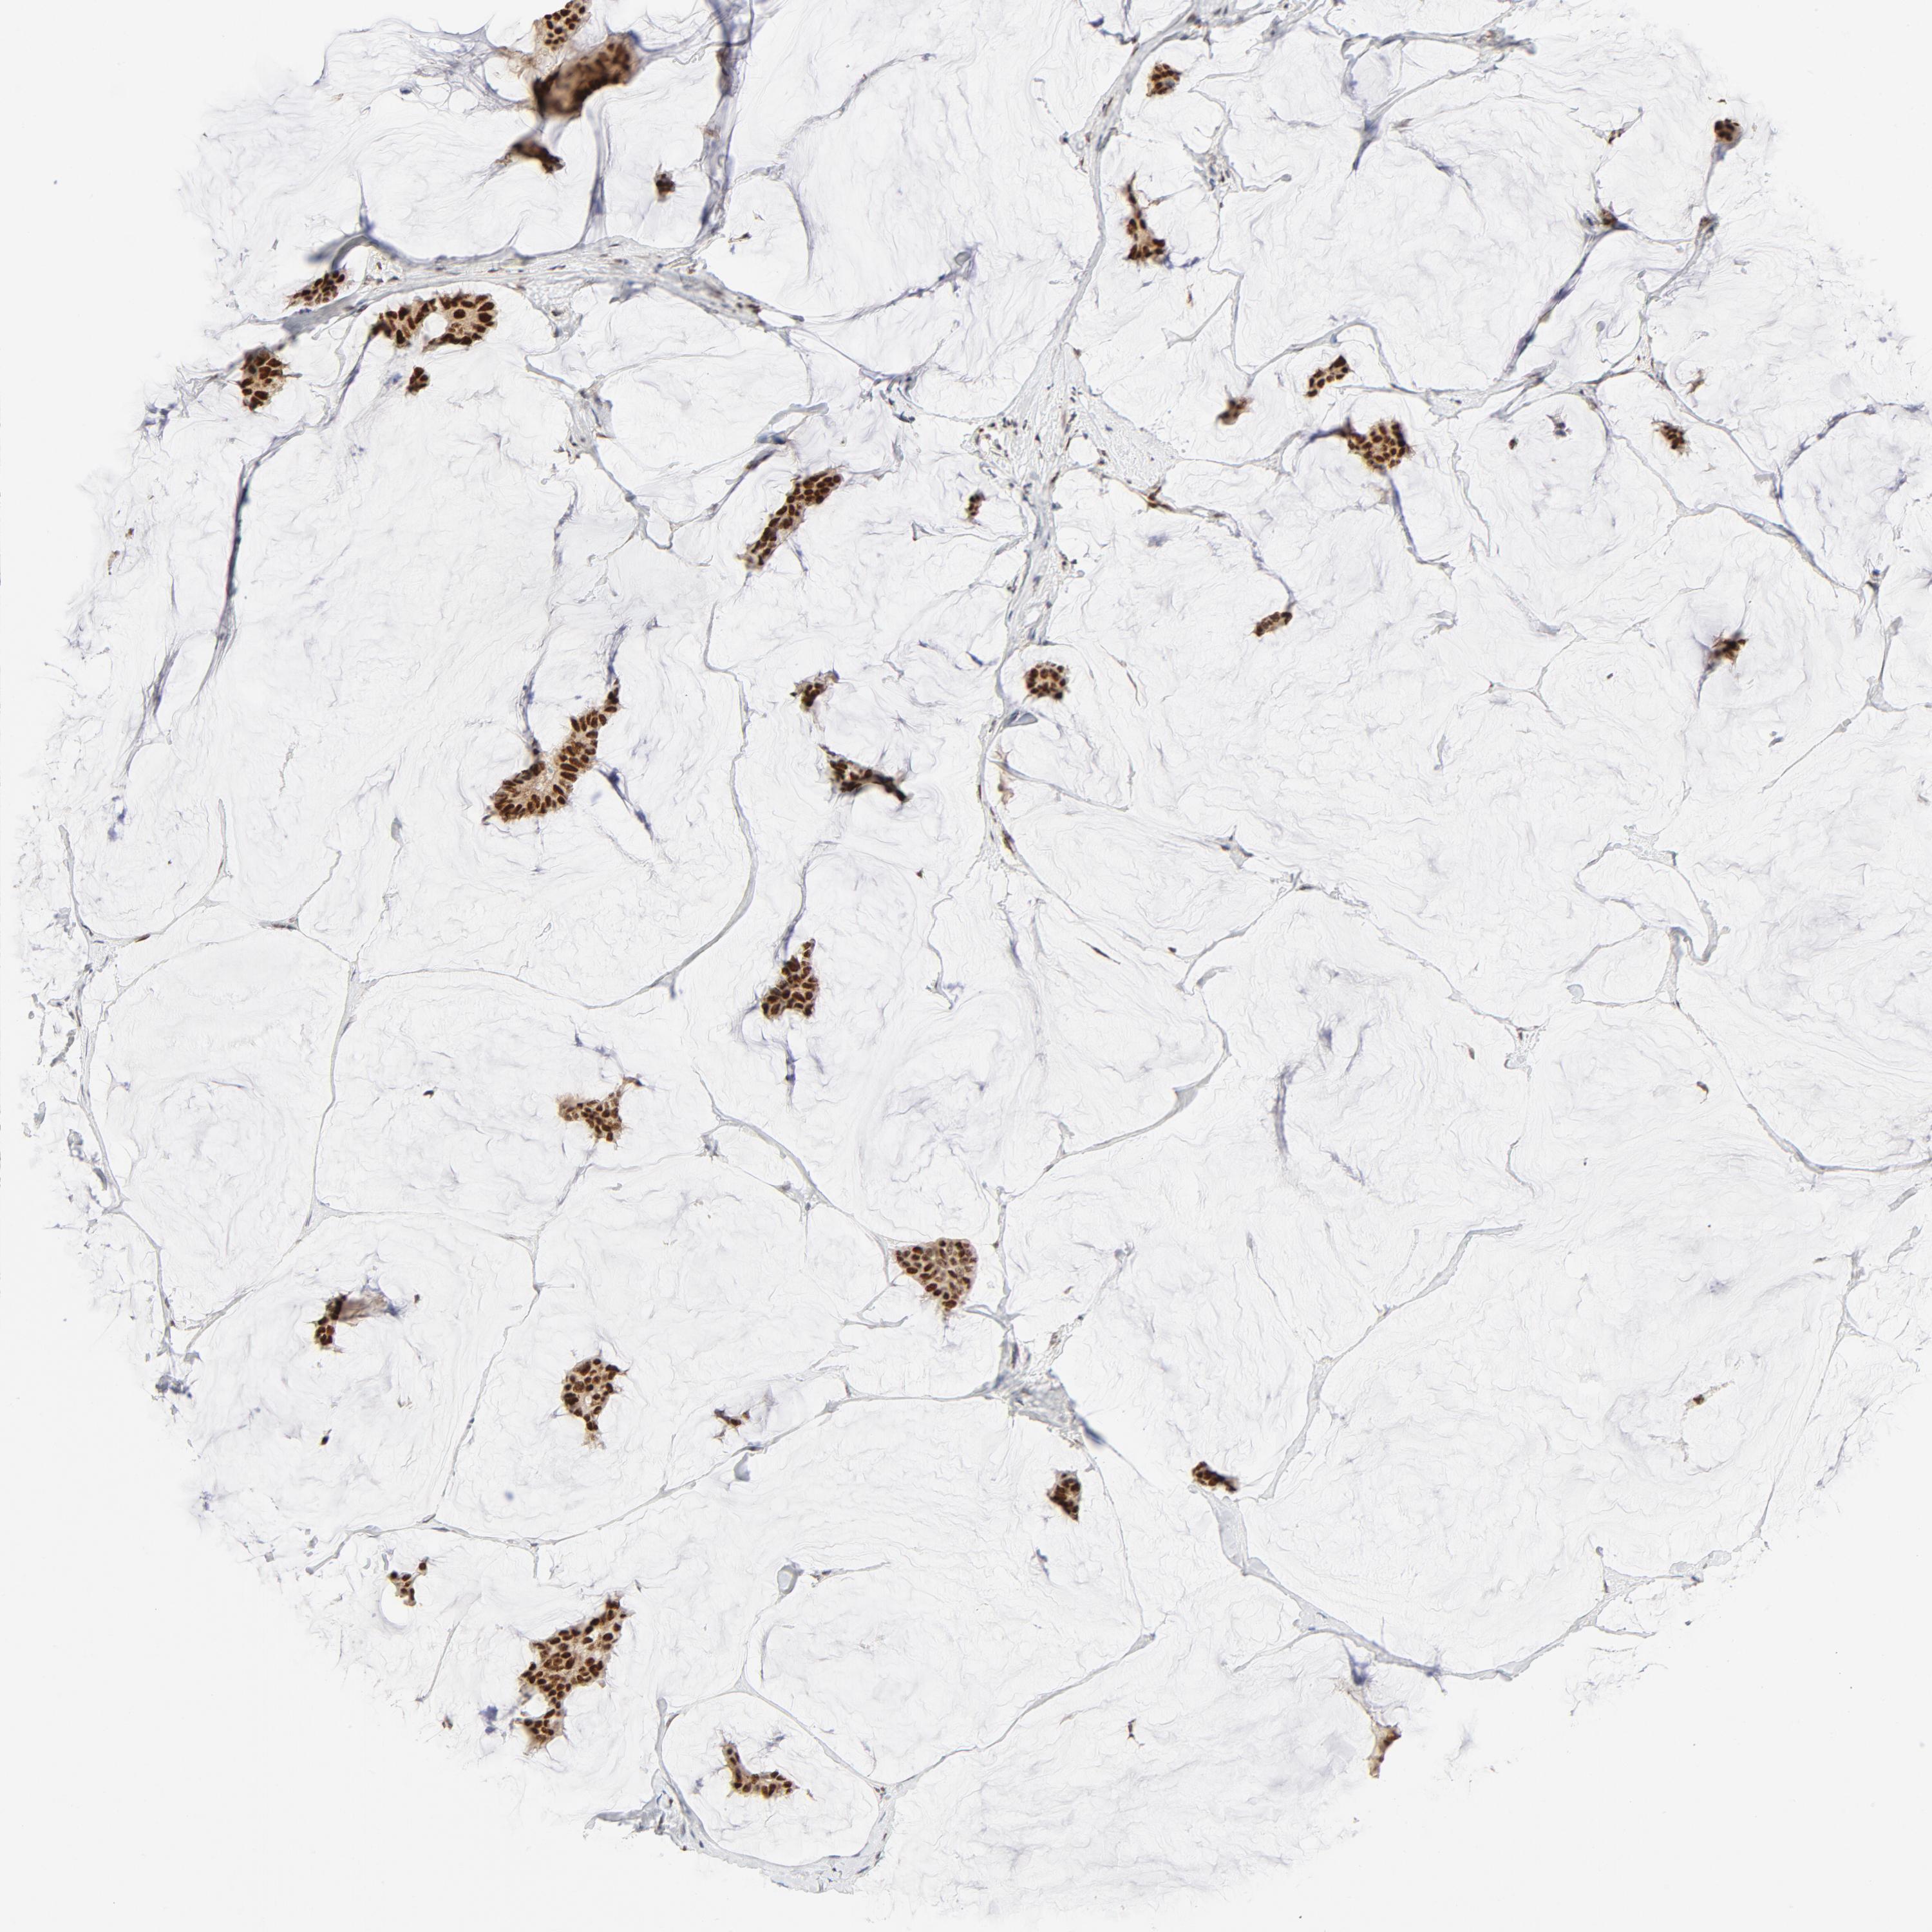

BRCA TCGA BRCA VALIDATION PROTEIN EXPRESSION

Breast cancer

Human cancer